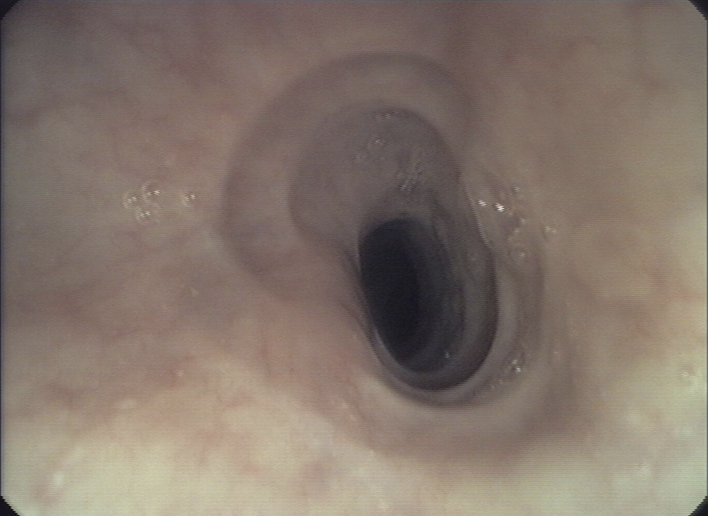

Figure 1

Endoscopic pictures illustrating the major endoscopic signs of EoE:

Panel A illustrates the endoscopic appearance of a healthy esophagus. Panel B represents a moderate inflamed esophagus with edema, longitudinal furrowing and mild non-stenosing trachealisation. Panel C shows a severe inflamed esophagus with edema, white exudates and deep furrowing. Panel D illustrate signs associated with remodeling such as stricture due to fixed esophageal rings.